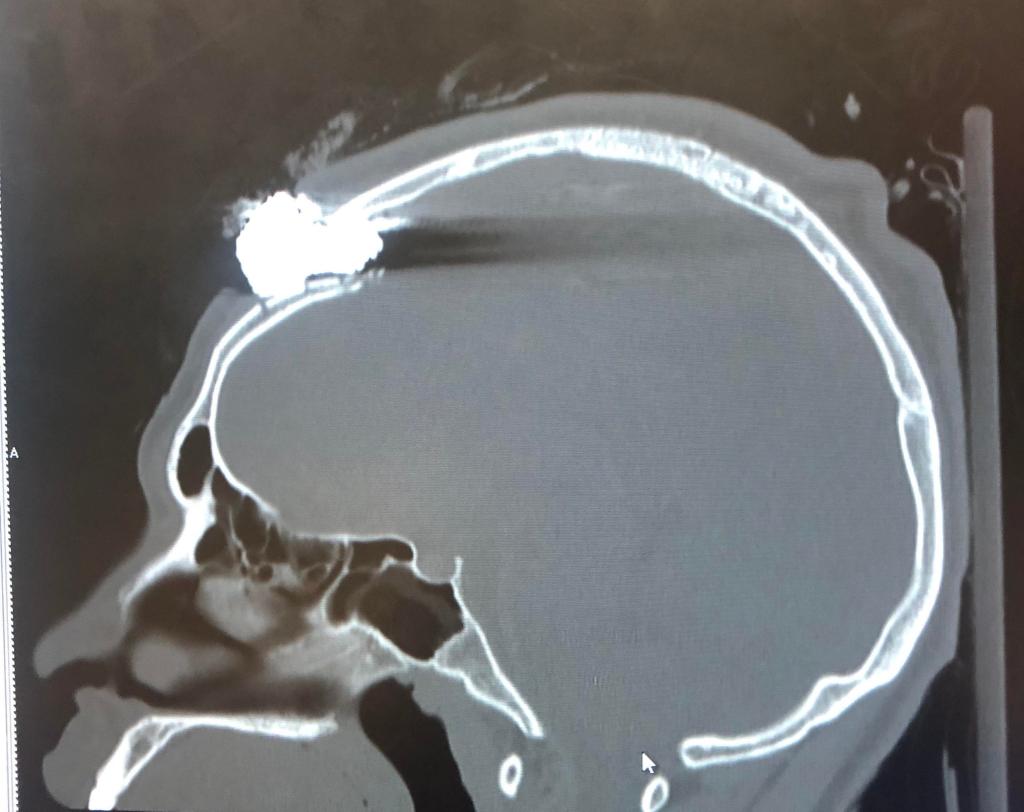

As we have witnessed in video after video, these weapons are instead being fired into crowds of protesters, often those who are peacefully assembled, without particular regard for where on the body they land. They are indeed ricocheting off of walls and barricades and are striking people in every part of the body. An article published in the British Medical Journal in 2017 found that the greatest risk from these weapons is when they are used at close range and the projectile strikes the face, head, or neck. These weapons have sufficient velocity to cause skull fractures and intracranial hemorrhage, causing permanent brain damage, or tear through the fragile arteries of the neck leading to rapid blood loss. When these projectiles impact the eye they can cause permanent blindness, or can penetrate through the fragile orbit of the eye and cause orbital fractures which can result in extensive brain injury and death. And while intentional targeting of the head and neck at close range is the most dangerous use of these weapons, firing at longer ranges is dangerous as well; while it decreases the velocity it also greatly decreases the accuracy, increasing the chances that even an appropriately aimed lower extremity shot will veer or ricochet and strike someone in a more vulnerable part of the body.

“These articles included injury data on 1984 people, 53 of whom died as a result of their injuries. 300 people suffered permanent disability. Deaths and permanent disability often resulted from strikes to the head and neck (49.1% of deaths and 82.6% of permanent disabilities).”

Though I have chosen not to include extensive images of these types of injuries on this blog post, they can be found easily enough online. One article from The Internet Journal of Surgery does include images of rubber bullets being retrieved from the neck, where they have lacerated the carotid artery, and from the abdominal cavity; but they aren’t for the faint of heart.